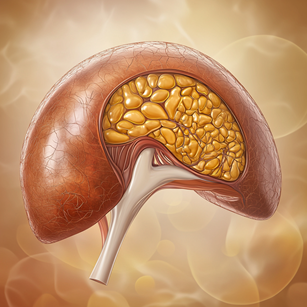

2. 알코올성 지방간

알코올성 지방간은 간세포에 지방이 축적된 상태입니다. 증상이 거의 없고, 간혹 상복부 불편감, 소화불량, 피로감을 느낄 수 있지만 대부분은 간기능 검사나 초음파 검사에서 이상 소견이 나와 병원에서 우연히 발견됩니다. 술을 많이 마시는 사람은 병원에서 진찰과 검사를 받는 것이 좋습니다. 다행히도 지방간은 술을 끊으면 정상으로 회복될 수 있습니다.

알코올을 많이 섭취하면 간에 지방이 쌓이는 이유는 간이 알코올을 대사하는 과정에서 생기는 여러 가지 변화 때문입니다. 간은 알코올을 해독하기 위해 1차적인 대사 장소로 작용하는데, 간은 지방보다 알코올을 우선적으로 처리하기 때문에 지방의 대사 능력이 떨어집니다. 결국 간에서 지방의 분해가 잘 이루어지지 않고, 지방이 축적됩니다.

또한 알코올은 간에서 지방 합성을 촉진하는 효소들을 활성화시키며, 대사 과정에서 중성지방이 많이 생성됩니다. 따라서 알코올을 많이 섭취할수록 간에서는 더 많은 지방이 만들어지고, 이 지방이 간에 축적되게 됩니다. 이러한 이유들로 인해 알코올을 많이 섭취하면 간에 지방이 쌓여 알코올성 지방간이 발생하게 됩니다.